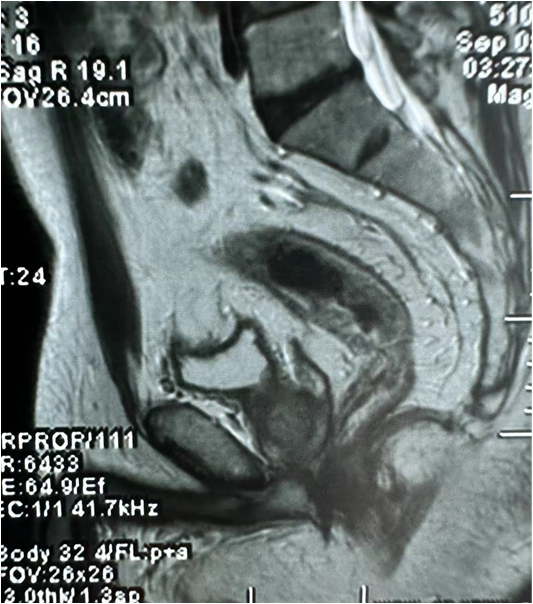

患者为57岁男性,体重最高曾经达到100kg,BMI=39,近期减重10kg,2年前无明显诱因下出现黑便,未予重视及治疗。4天前至门诊查肠镜提示:距肛门10cm见环1/2周不规则新生物,质硬,表面糜烂,MRI提示直肠肠壁增厚。经MDT讨论,拟行腹腔镜直肠根治术。

术前腹部MRI